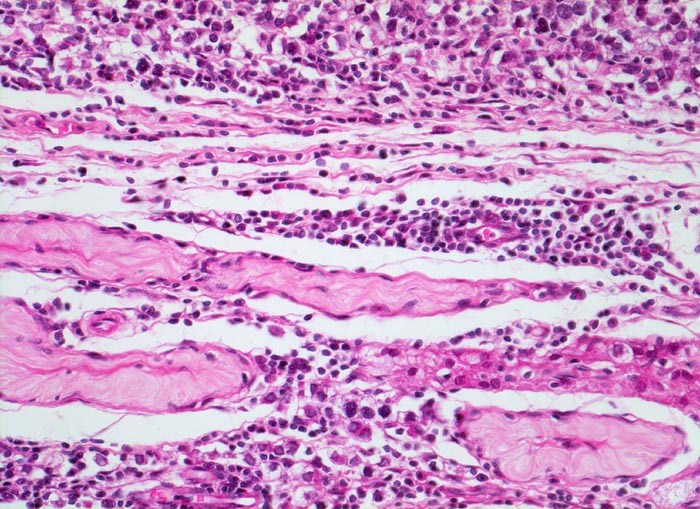

• Unterschiedlich breite solide Tumorzellstränge aus monomorphen Zellen mit grossen hyperchromatischen Kernen und einem solitären zentralen prominenten Nukleolus. Reichlich helles Zytoplasma mit scharfen Zellgrenzen.

• Schmale bindegewebige Septen mit Kapillaren und lymphoplasmazellulärem Entzündungsinfiltrat.

• Tubuläre Atrophie des angrenzenden Hodenparenchyms. Einige Hodentubuli enthalten stark atypische pleomorphe Keimzellen (Keimzellneoplasie in situ).